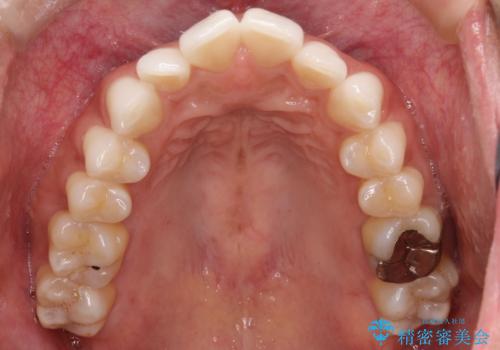

- 前歯の重なり(叢生)をきれいに整えたいという主訴でご来院されました。

精密検査の結果、歯を並べるためのスペースが不足していましたが、抜歯をせずに改善したいというご希望があったため、IPR(歯の側面をわずかに削る処置)と、奥歯を後ろに動かす「遠心移動」を組み合わせる計画を立案。透明なマウスピース装置であるインビザラインを使用し、無理のない範囲でスペースを確保しながら歯列を整えることとしました。

治療では、マウスピースの設計に基づき、奥歯から順に後ろへ移動させる遠心移動を行い、前歯のためのスペースを作りました。同時に、数箇所の歯の間にIPRを施すことで、歯の健康に影響のない範囲で精密に隙間を確保しました。